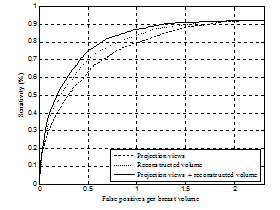

그림 1. 제안 방법에서 특징 정보 추출에 활용한 영상에 따른 FROC 분류 성능 비교. 단면영상과 투영영상 모두에서 특징 정보를 추출할 때(projection views+reconstructed volume) 분류 성능이 향상됨을 보임.

In digital breast tomosynthesis (DBT), image characteristics of projection views and reconstructed volume are different and both have the advantage of detecting breast masses, e.g. reconstructed volume mitigates a tissue overlap, while projection views have less reconstruction blur artifacts. In this paper, an improved mass detection is proposed by using combined feature representations from projection views and reconstructed volume in the DBT. To take advantage of complementary effects on different image characteristics of both data, combined feature representations are extracted from both projection views and reconstructed volume concurrently. An indirect region-of-interest segmentation in projection views, which projects volume-of-interest in reconstructed volume into the corresponding projection views, is proposed to extract combined feature representations. In addition, a boosting based classification with feature selection has been employed for selecting effective feature representations among a large number of combined feature representations, and for reducing false positives. Experiments have been conducted on a clinical data set that contains malignant masses. Experimental results demonstrate that the proposed mass detection can achieve high sensitivity with a small number of false positives. In addition, the experimental results demonstrate that the selected feature representations for classifying masses complementarily come from both projection views and reconstructed volume.Author information

- 최근 digital breast tomosynthesis (DBT)가 새로운 유방 영상 촬영술로 주목을 받고 있습니다. DBT의 2차원 투영영상(projection views)과 3차원 단면영상(reconstructed volume)은 상보적 영상 특성을 가지고 있어, 병변(mass) 자동 검출에 두 영상 정보를 모두 분석하는 것이 효과적 입니다. 이를 위해 본 논문은 두 영상에서 병변의 융합 특징 정보를 추출하고, boosting 및 다중 분류기 기반 병변 특징 선택/분류 방법을 제안하였습니다. 실험을 통해 두 영상 정보를 모두 분석 시 병변 분류 성능이 향상됨을 보였고 (그림 1), 분류에 중요한 병변 정보를 포함하여 자주 선택된 특징 정보들이 두 영상에 모두 분포하여 상보적임을 보였습니다 (그림 2). 또한 기존 정보 융합 방법 대비 우수한 분류 성능을 보여 (그림 3) DBT 투영영상과 단면영상 특징 융합 분석, 위양성 감소 (그림 4)에 효과적임을 보였습니다. 본 연구는 다중 영상 융합 분석, DBT 영상 특징 분석에 관심 있는 연구자들에게 도움이 될 좋은 정보라 생각합니다.